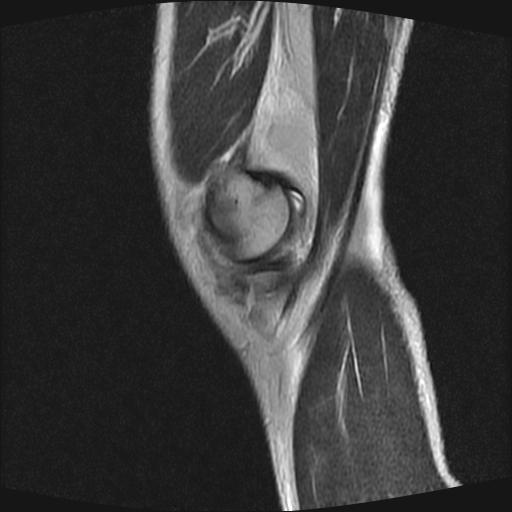

标题: MRI1265:男性40岁,右膝关节 [打印本页]

标题: MRI1265:男性40岁,右膝关节

40岁男性,右膝关节外伤,x光平片示,髁间隆突撕脱骨折。

1、前交叉韧带撕裂;

2、外侧半月板后角撕裂;

3、关节腔积液。

前交叉韧带撕裂,关节腔积液.

半月板1-2级损伤   前交叉韧带撕裂伤   关节腔少量积液  诸骨未见新鲜外伤性改变

髁间隆突撕脱骨折;内侧副韧带损伤。

内侧副韧带撕裂及关节腔积液是肯定的,但是前交叉撕裂确定吗?会不会有容积效应的因素,因为前一张前交叉显示清楚,连续性良好,且较光滑。请问楼主有关节镜支持吗?我们医院也经常有这样的患者,但苦于没有关节镜,而无法对照、证实(除非完全断裂),出现了不同的诊断结果只能毫无意义的争论。

1、前交叉韧、内侧副韧带撕裂;

3、关节腔积液。4、髁间脊撕脱骨折。

除了关节积液外并无韧带撕裂,acl胫侧附着点有2束,正常情况下脂肪信号。此病例应加做压脂像以便观察是否有骨损伤。